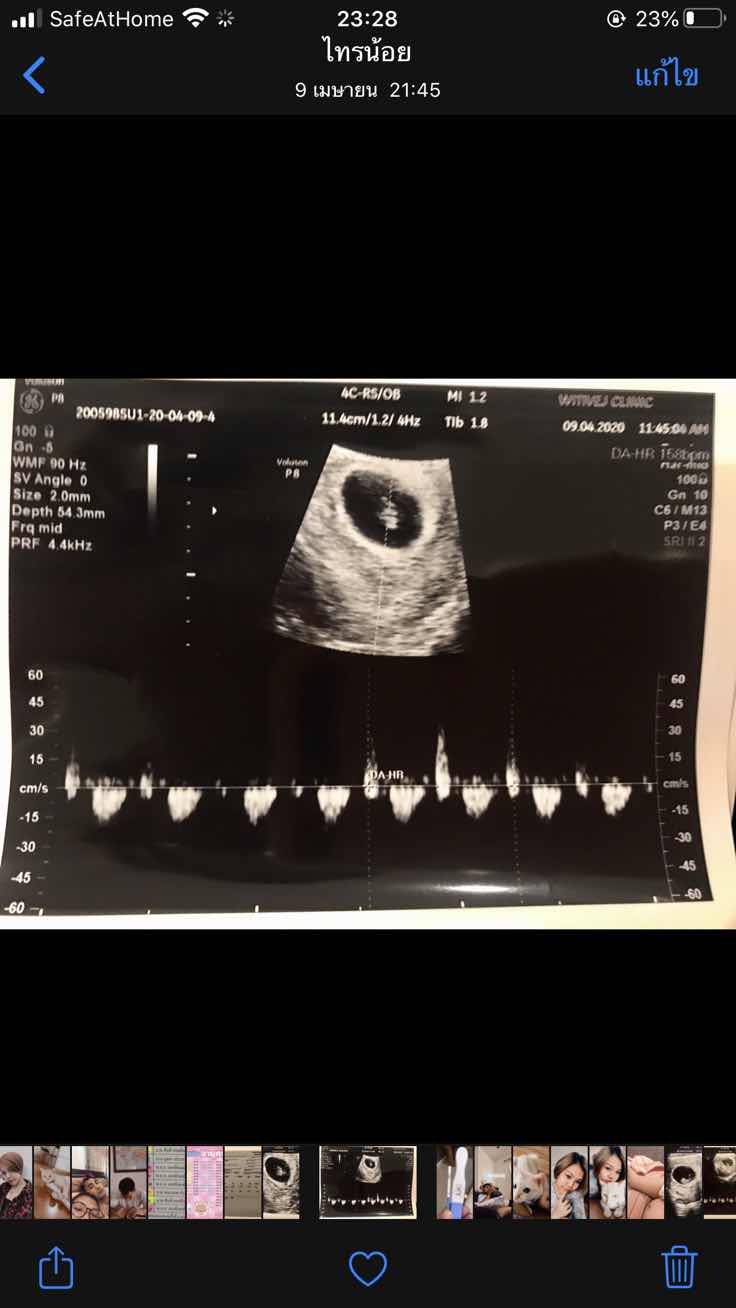

พอดีตอนนี้ตั้งครรภ์ได้7วีค อยากไปซาวแต่กลัวไม่เห็นน้อง แม่ๆเห็นตัวน้อง หัวใจ น้องเต้นตอนกี่วีคกันคะ?